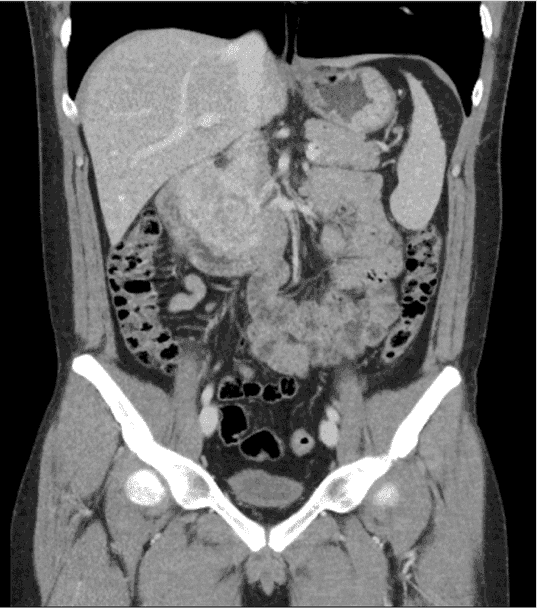

A proper workup of GIST requires imaging. GIST is best evaluated by cross-sectional imaging such as computed tomography (CT). They appear on CT scans as solid masses with smooth contours that are easily identified by IV contrast (Figure 1). Larger masses can show evidence of hemorrhage, necrosis, and degenerative areas on CT imaging, creating cavities or cysts that may contain air, air and fluid, or contrast medium. CT imaging can also assess for adjacent organ invasion and metastases [11].

Figure 1. Computed Tomography Scan of the Abdomen and Pelvis with IV Contrast.